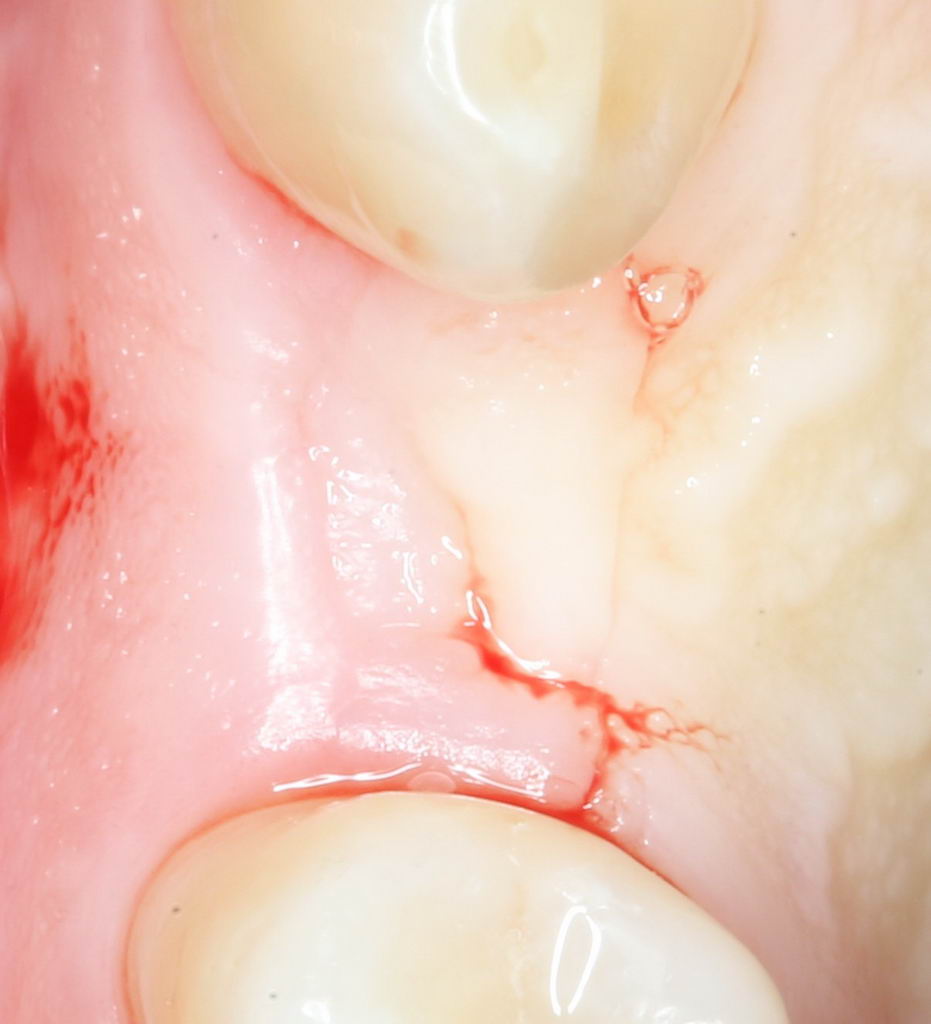

Для окончательного формирования десневого контура, осталось только наложить швы.

Наложение швов.

Помните, в самом начале операции мы планировали наложение швов с учётом будущего вестибулярного смещения лоскута? Так вот, теперь у нас есть возможность не просто сместить, но и зафиксировать вестибулярный лоскут. Делается это, так сказать, с подворотом края снаружи:

Обратите снимание, что альвеолярный отросток в этой области стал более объемным. Этого удалось добиться без всяких остеопластических операций или гингивопластики, путём простого перемещения тканей.